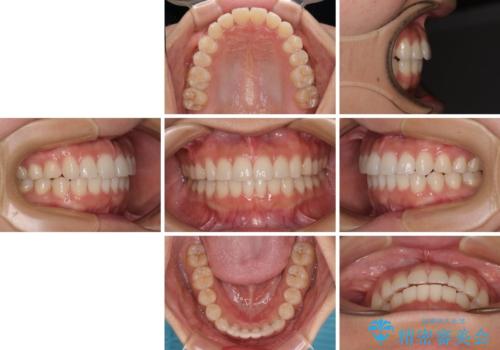

治療中は大きなトラブルもなく、予定の1年半でスムーズに治療を終えることができました。

ワイヤー矯正でもインビザラインでも、どの装置でも対応可能でしたが、安価で楽して素早く治療を終えたいとのことで、メタルブラケット装置による矯正治療を行うこととしました。